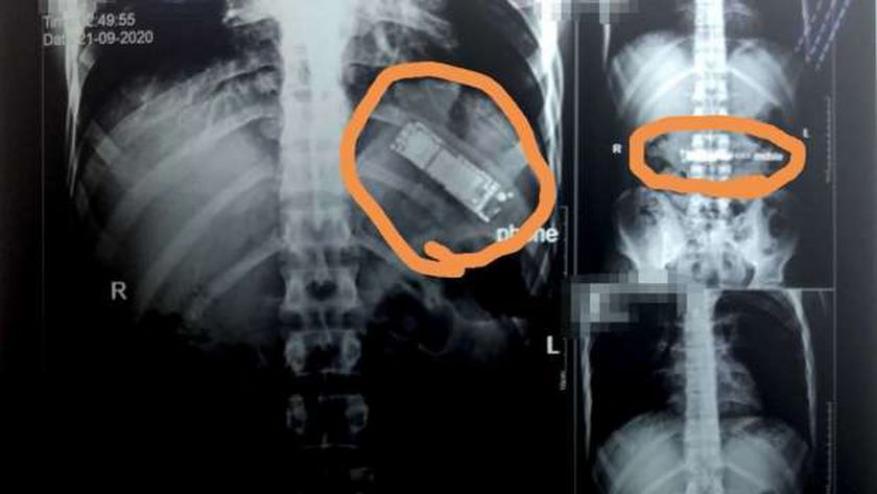

كشفت فحوص بالأشعة أجريت لمريض بمستشفيات بنها الجامعية في مصر، عن وجود هاتف محمول في معدته بقي هناك بعد أن قام بابتلاعه منذ 7 أشهر.

وقال الدكتور محمد الجزار، استشاري أورام الصدر وأستاذ جراحة القلب والصدر والمناظير بكلية الطب في جامعة بنها، إنه تم استقبال المريض اليوم، من مدينة كفر شكر بالقليوبية، وتم إجراء أشعة تليفزيونية على الصدر والبطن، حيث تم اكتشاف وجود هاتف محمول بمعدته.

وأوضح الجزار، أن المريض أكد أنه ابتلع الجهاز منذ 7 أشهر على سبيل المداعبة مع أصدقائه دون أن يعلم أي فرد من أبناء أسرته، موضحا أنه بسؤاله عن سكوته طوال هذه الفترة، أكد أنه كان يظن أن التليفون سيخرج بمجرد حدوث استرجاع بالمعدة مرة أخرى، إلا أن هذا لم يحدث حتى الآن.

وتابع الطبيب، أنه تم تحويل المريض لقسم الجراحة العامة بالمستشفى، ويتم إعداده حاليا ووضعه بقائمة الجراحات تمهيدا لإجراء الجراحة سريعا والتعرف على نوع التليفون وكيفية ابتلاعه